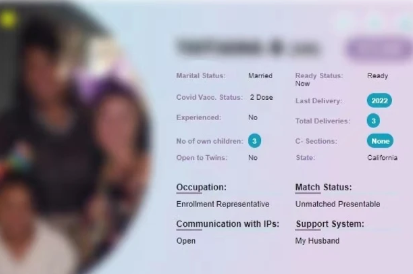

RSMC擁有近30年經驗,專責律師在孩子出生前處理好親權問題。選擇美國合法代孕,就是選擇最專業可靠的求子之路。選擇美國 RSMC, 就是選擇最專業可靠的生殖機構來完成您的求子夢想! 若您想開始挑選代理孕母,或了解更多療程信息,歡迎聯繫我們或添加Line / wechat: rsmctw,或加入whatsapp:+1 858-342-6046。

我們擁有北美前三大卵子銀行,由本院醫師親自管理,以羅馬的光明與生育女神命名。捐卵者年齡19-29歲,包含西洋、華裔等多種族選擇,目前美國有將近40個醫院診所向我們採購卵子。所有捐卵者均通過嚴格的生育力檢查、基因篩查、心理評估、IQ測驗,並由專業律師協助放棄親權。我們的遺傳病檢查高達202項,遠超過FDA標準,因為我們相信,高品質高標準,才能夠為求子心切的準父母們負責。